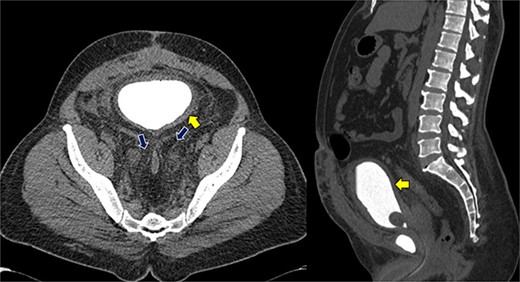

Despite initial stability, the patient’s creatinine levels rose again, and hydronephrosis worsened. Left percutaneous nephrostomy and antegrade stenting ultimately stabilized his creatinine, and he now undergoes annual stent exchanges. Follow-up abdominopelvic MRI T2WI revealed PL surrounding the urinary bladder and rectum (Fig. 2, red arrow). Additional imaging with axial and sagittal CT cystogram showed urinary bladder wall thickening (Fig. 3, yellow arrow) accompanied by extensive PL and fat stranding (blue arrows).

Axial and sagittal CT cystogram demonstrating urinary bladder wall thickening (yellow arrow) with PL and extensive fat strandings (blue arrows).